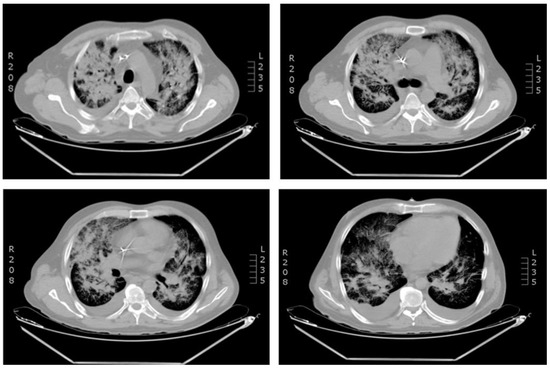

Severe Coronavirus HCoV-NL63 Pneumonia in a Patient Receiving Blinatumomab with Secondary Antibody Deficiency in COVID-19 Times

by Claudia C. Paredes-Amaya, Lorena Matta-Cortes and Andrés Felipe Zea-Vera

Introduction: Human coronavirus NL63 (HCoV-NL63) is one of four common human respiratory coronaviruses. It causes lower respiratory tract infections in young children, elderly and immunosuppressed people, which could result in fatal outcomes. In this time of pandemic, we want to highlight the importance of other coronaviruses infection besides SARS-CoV-2, especially in a patient with underlying conditions like acute lymphoblastic leukemia, receiving immunosuppressive therapy that could result in humoral secondary immunodeficiencies. Case report: We present the case of a 44-year-old Colombian man with acute lymphoblastic leukemia who developed HCoV-NL63 pulmonary infection after the first month of treatment with blinatumomab complicated with severe secondary hypogammaglobulinemia. HCoV-NL63 was detected by multiplex PCR, and HCoV-NL63 viral pneumonia was diagnosed. Hypogammaglobulinemia was studied by determining serum immunoglobulins levels and protein electrophoresis. The treatment consisted of supportive therapy and replacement with intravenous immunoglobulins. After therapy, the patient improved his oxygenation, and the infection was resolved in a few days. Conclusions: This case highlights the relevance of other coronaviruses infections besides SARS-CoV-2 in patients receiving immunosuppressive therapy who develop secondary antibody deficiency, and the importance of replacement therapy with intravenous immunoglobulins at early stage of infection with HCoV-NL63. Full article

Show Figures